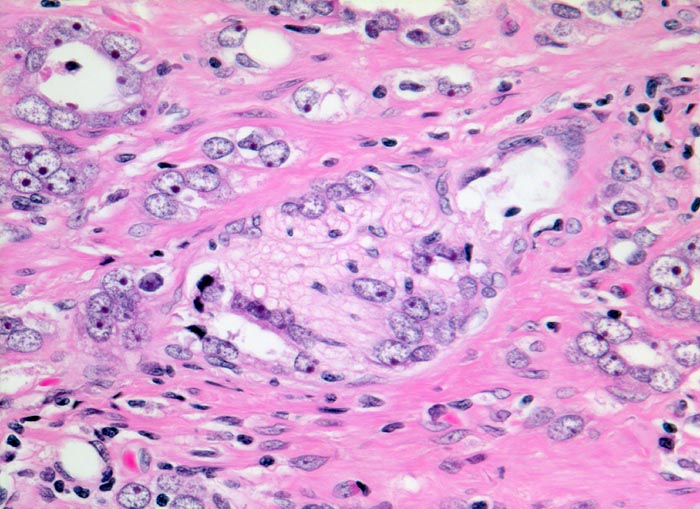

Adenokarzinom der Prostata: Nervenscheideninvasion

Das Karzinom bildet an dieser Stelle kleine schlecht geformte Drüsen entsprechend einem Gleason Grad 4. Die Tumorzellen zeigen hier deutliche Nukleolen. Einzelne Karzinomdrüsen infiltrieren die Perineuralscheide eines peripheren Nerven.

Adenokarzinome der Prostata liegen bevorzugt in der Aussendrüse, wo auch die peripheren Nerven lokalisiert sind. Eine Invasion der Perineuralscheiden lässt sich in fortgeschrittenen Karzinomen oft nachweisen.